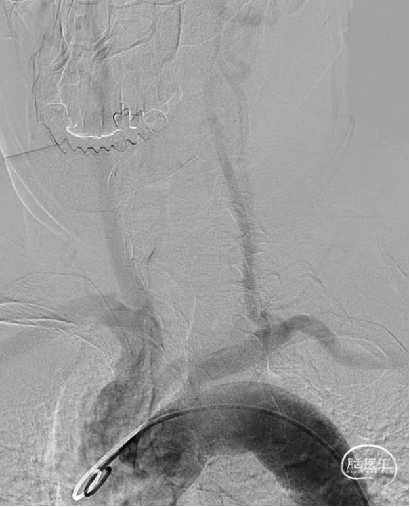

成功穿刺左侧远桡动脉后,置入6.5F薄壁桡动脉鞘,V18+Fastrack微导管支撑下,DA顺利进入L-V1段。

0.014 Synchro微导丝携Fastrack微导管至L-P1,引入4mm*20mm Tubridge血流导向密网支架。

Tubridge血流导向密网支架释放,回拉定位,逐步推挤释放支架。

释放完毕后跟进支架导管,回收输送导丝,微导丝成袢行支架内按摩。

术后影像:

动脉瘤愈合,支架内血流通畅。